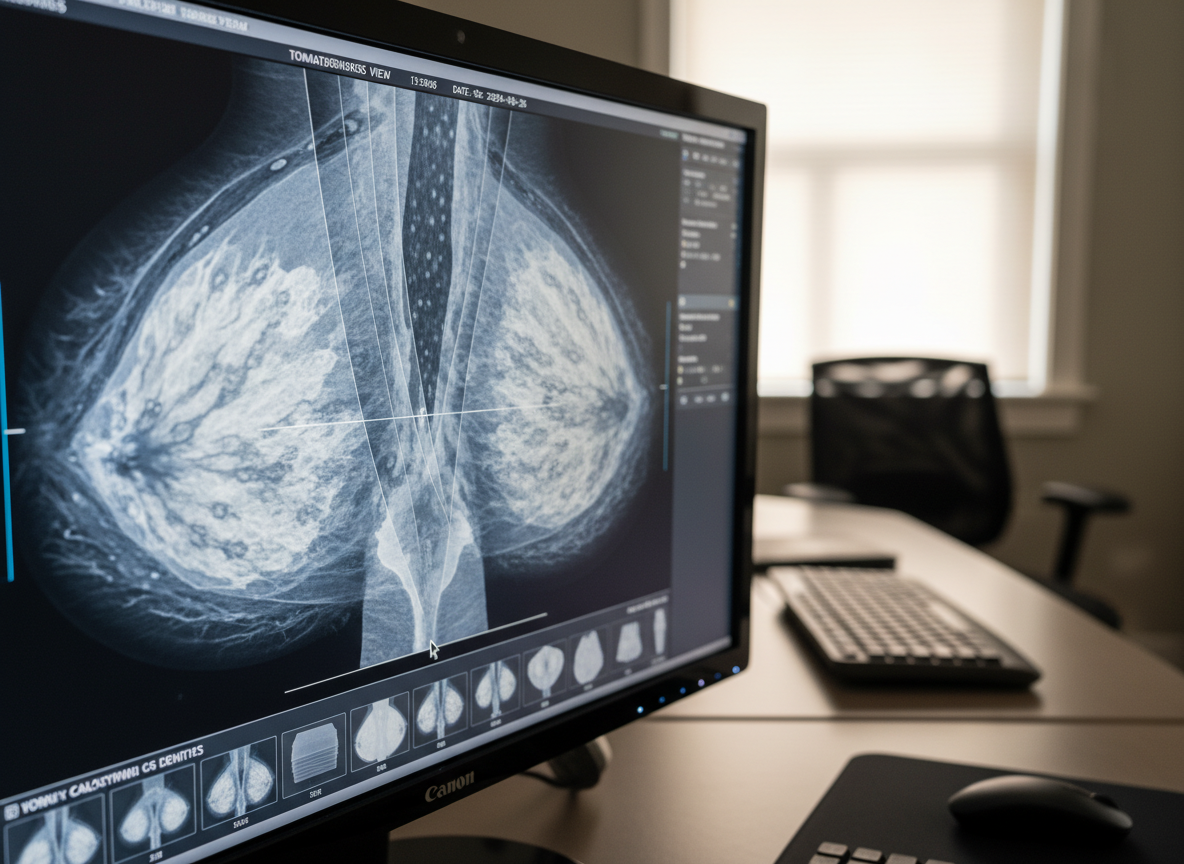

난치성 암으로 알려진 삼중음성유방암은

그동안 치료가 매우 까다로운 분야였습니다.

이런 상황에서 최근 인공지능(AI) 기반의

혁신적인 연구 결과가 발표되어

많은 환자분들에게 큰 희망이 되고 있어요.

고대구로병원 종양내과 서재홍 교수팀의 연구는

AI 기반 3D 도킹 분석이라는 최첨단 기술을 활용해

오랫동안 사용되어 온 약물에서

새로운 항암 효과를 찾아냈다는 점에서

매우 의미가 깊습니다.